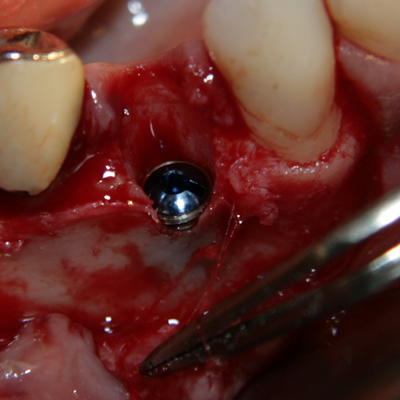

Имплантатът е поставен. За непрофесионалисти снимката е изключително зловеща - кръв, инструменти, зъби и нагледна човешка анатомия... В действителност обаче поставянето на зъбни импланти е една от най-атравматичните операции в областта на Оралната и Лицево - челюстната хирургия: не се отнема никакъв костен обем (както е при екстракцията на един ретиниран мъдрец например), поставя се стерилно тяло в костта, не се отпрепарират тъканите нашироко (както е при операцията на киста, остеомиелит или, недай боже, тумор). Изключително радко се налага антибиотичен прием постоперативно - обикновено при извършване на костна пластика в голям обем. Повече информация за приложението на антибиотиците в имплантологията прочетете тук...